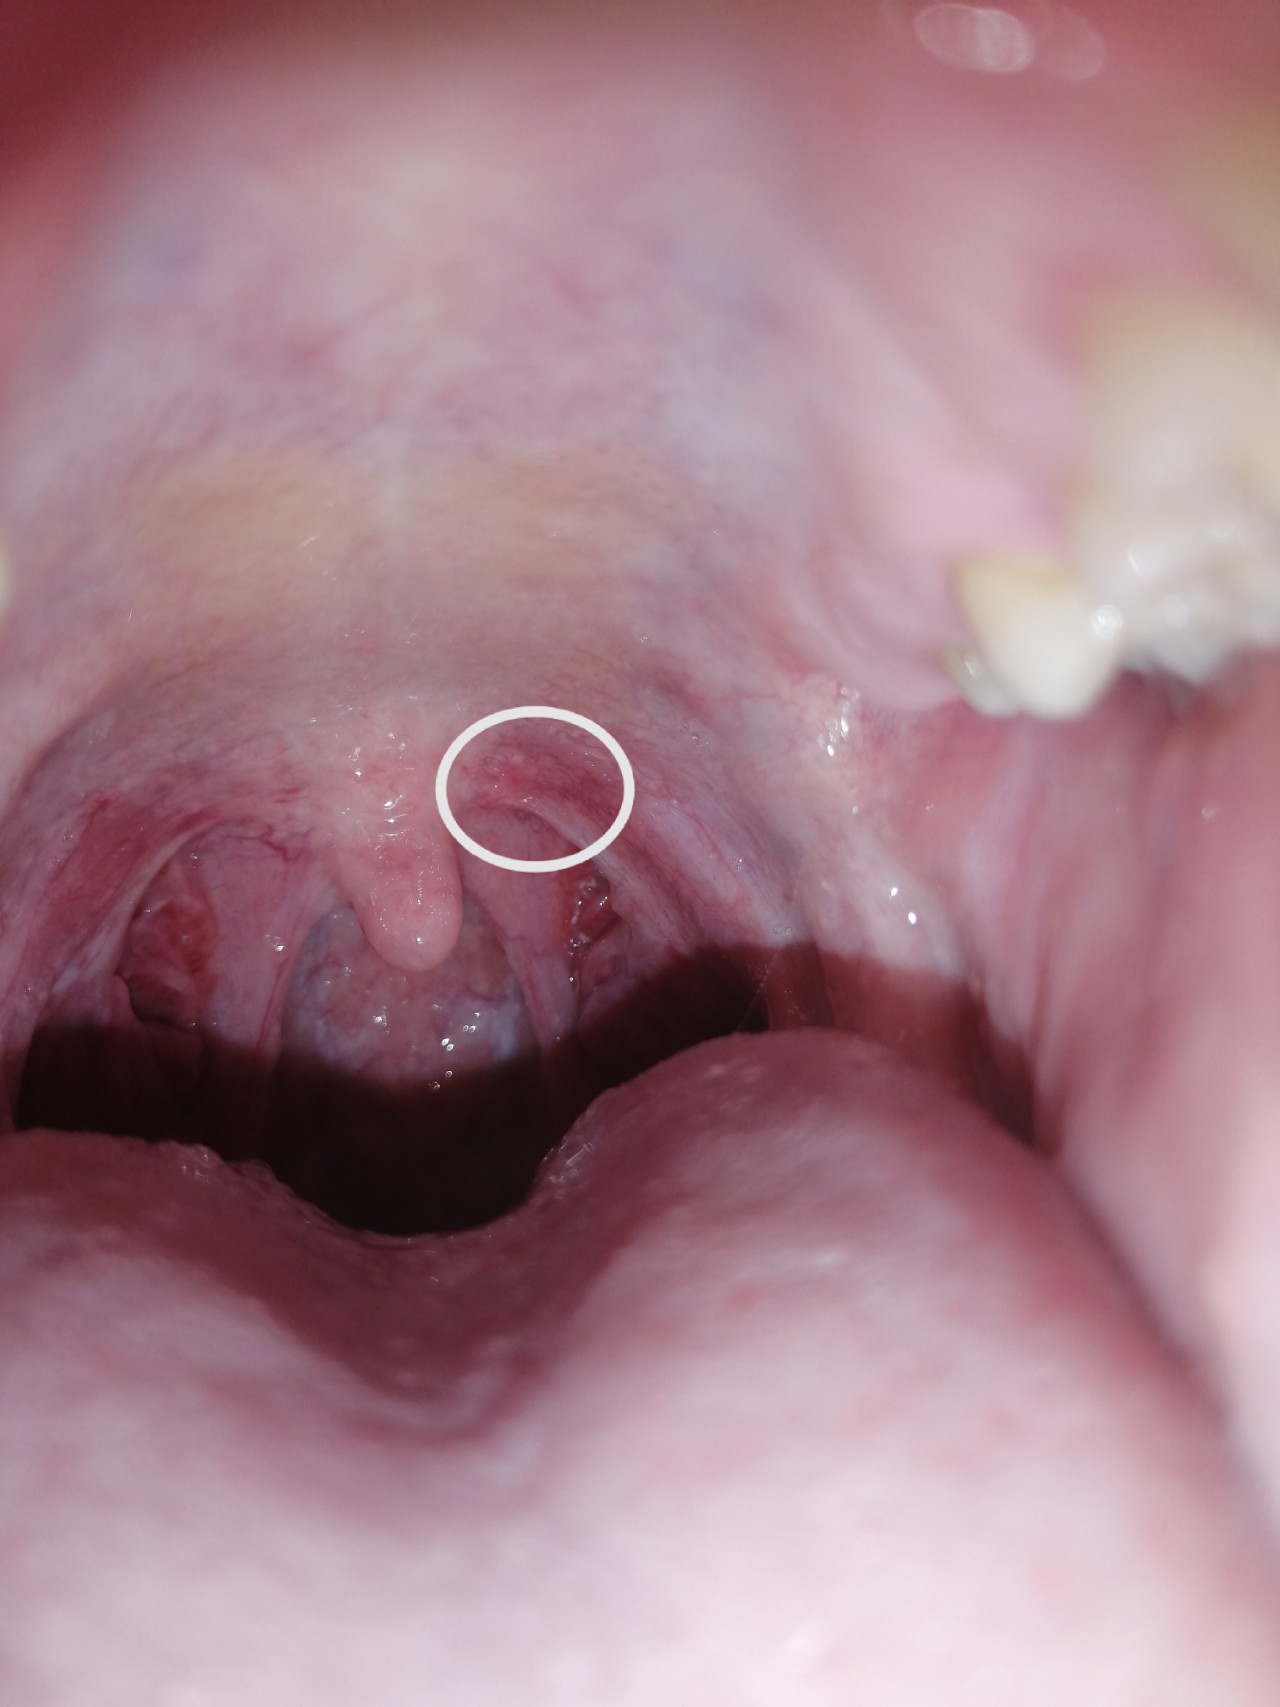

Вопрос лору: Здравствуйте, несколько дней назад на миндалине появилось красное пятно, внутри есть небольшая синяя прожилка . По виду напоминает кровоподтёк, . . .

Вопрос лору: Здравствуйте, три недели назад появилась такое вот ярко-красное пятнышко на миндалине . Ничего не болит, аллергии нет . Что это может быть? . . .

Красное пятно на миндалине что это На миндалинах красные точки Здравствуйте, уважаемые читатели! Появились красные яркие точки на гландах? Что это такое?

Вопрос лору: Здравствуйте, заболело горло, есть хронический танзилофарингит, на миндалине обнаружила красное пятнышко, болит . Что это может быть?

Так как только одно пятнышко красное . До врача аж через 2 недели талон . . бывает ли прыщ на миндалине? Когда их несколько это не так на тостораживает, у меня всего один:((( всякого надумала себе .

Пятнышко может быть налетом, который образуется в результате воспаления - как правило оно обусловлено отторжением эпителия, умершими клетками, микробами, которых п полости рта уйма .